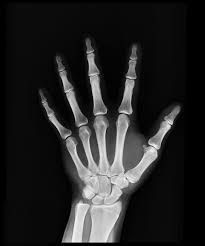

An urgent care X-ray is a diagnostic imaging service used to view bones and certain internal structures of the body. These images help medical providers diagnose injuries and conditions quickly so that treatment can begin right away.

Urgent care centers use X-rays to identify:

- Broken or fractured bones

- Sprains and joint injuries

- Dislocations

- Chest conditions such as pneumonia

- Foreign objects in the body

- Certain abdominal issues